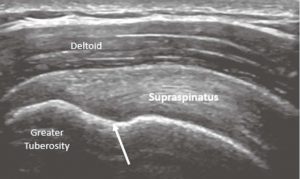

Ultrasound waves interact with anatomical structures, such as muscles and tendons, giving each one a specific appearance when imaged. In short axis, the muscle has a primarily hypoechoic/dark appearance with speckles (this is often referred to as “starry-eyed” due to the visualization of the perimysial tissue which is more hyperechoic/white). Long-axis imaging displays the linear appearance of the muscle fascicles, and this differs depending on the type of muscle imaged (i.e., parallel, bipennate, unipennate or circular).4 Tendons are denser and have a more hyperechoic fibrillar appearance in long axis. In short axis, the tendon appears hyperechoic and has been likened to bristles on a brush (Figures 2 and 3).5

This patient’s right Achilles tendon is normal, with a fibrillar appearance in long axis (Figure 2) and a brush-on-end hyperechoic appearance in short axis (Figure 3). The left Achilles tendon is abnormal, demonstrating signs of tendinosis such as thickening (arrows) and diffuse hypoechoic echotexture, however there is no fiber disruption or fluid collections which would indicate tearing.

The supraspinatus tendon’s normal appearance has a curved contour deep to the deltoid, and the greater tuberosity has a notch at the insertion. It is at this notch that it is common to see anisotropy, which should not be confused with a tear (Figure 7).